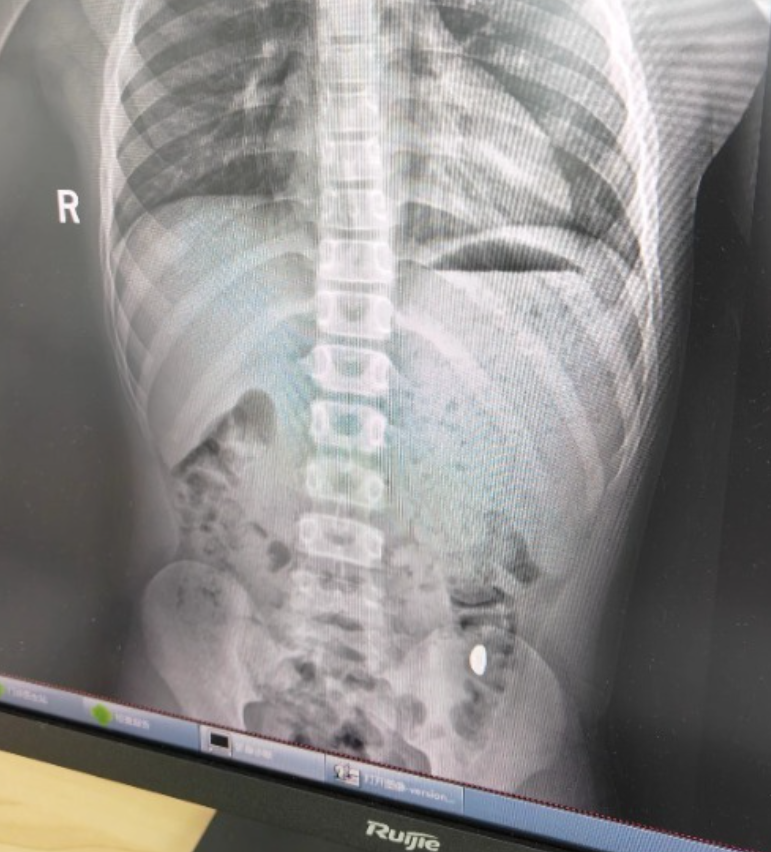

右下加亮点为金豆